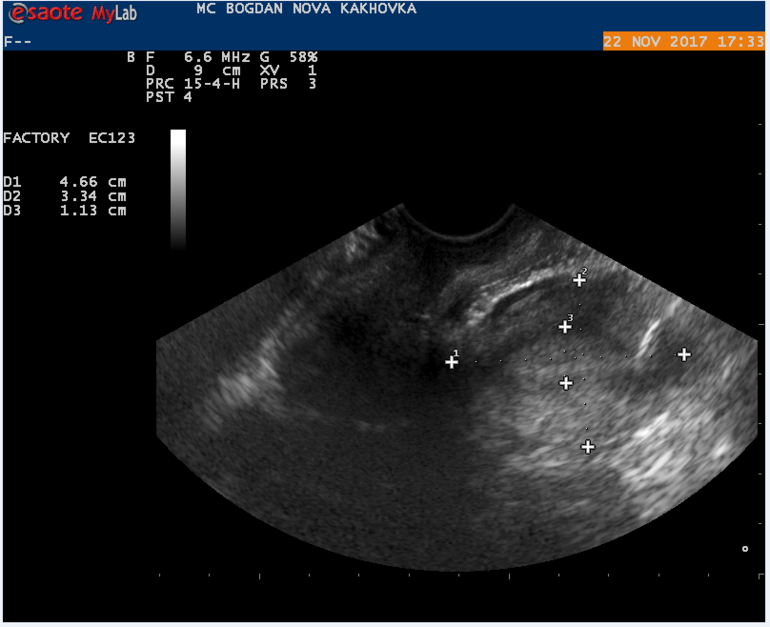

Мой результат УЗИ на 16 ДЦ Кто что может сказать? Тест на О положительный на 13 и 14 ДЦ.

в протоколе узи не слова о наличии доминантного фолликула, поэтому вряд ли была или будет овуляция в ближайшие дни

Может не увидели жт? Или не успело сформироваться.. Лично не сталкивалась, но читала, что бывает его не видят. Ведь эндик второй фазы у вас.

судя по узи овуляции не было,доминантного фолликула нет. хотя желтое тело может позже сформироваться